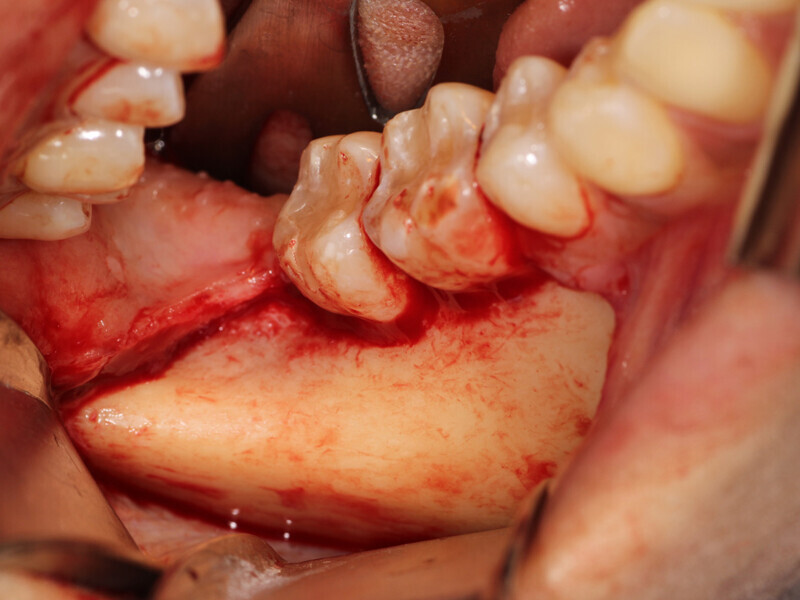

Fig. 3: A full thickness flap was created to expose the deficient facial aspect of the edentulous premaxilla that will receive augmentation to accommodate implant placement.